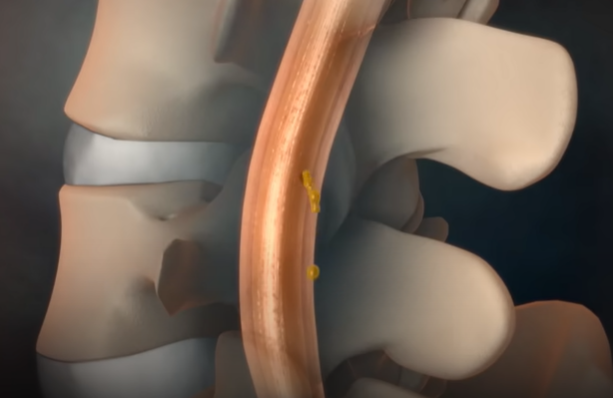

뇌척수액 누출로 인한 두통

뇌척수액이 척추 어디에선가 새어 빠져나가게 되면

그 위에 떠 있던 뇌가 아래로 주저앉으면서 심각한 두통을 유발한다.

물주머니에 뇌가 담겨 있다고 생각하면 된다. 물이 150cc 정도 있는데 그 안에 1.4kg 정도의 뇌가 떠 있다고 보면 된다. 이 무게를 실제 못 느끼는 것은 부력 때문인데, 물 주머니가 새는 경우가 있다. 그러면 물이 빠지면서 부력이 없어지니까, 뇌가 주저앉으면서 심한 두통을 일으킬 수 있는 것이다. 고통지수 10이라고 하면 10점 이상의 도통이라고 할 수 있다. 특징은 서있을 때는 척수액이 빠지기 때문에 굉장한 통증을 유발하는데, 누우면 최대 1분 내로 두통이 없어진다. 그러나 다시 일어나면 척수액이 더 빠지고 뇌가 밑으로 처지면서 극심한 통증이 재발한다.